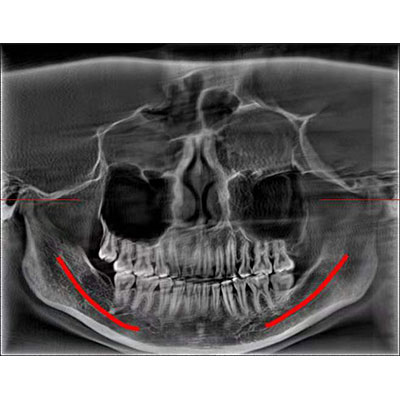

該款牙科CBCT產(chǎn)品采用動(dòng)態(tài)平板探測(cè)器,獲得三維圖像的同時(shí)還具有數(shù)字化全景功能,廣泛應(yīng)用于口腔頜面外科、正畸科、正頜外科、種植科、牙體科、顳下頜關(guān)節(jié)科等術(shù)前術(shù)后。

通過三維容積影像,提取高清口腔全景影像。

專有圖像校正技術(shù),去除金屬偽影,提高圖像分辨率。